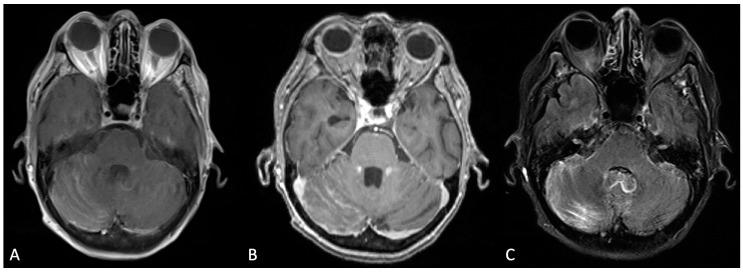

The present review aimed to establish an understanding of the pathophysiology of leptomeningeal disease as it relates to late-stage development among different cancer types. For our purposes, the focused metastatic malignancies include breast cancer, lung cancer, melanoma, primary central nervous system tumors, and hematologic cancers (lymphoma, leukemia, and multiple myeloma). Of note, our discussion was limited to cancer-specific leptomeningeal metastases secondary to the aforementioned primary cancers. LMD mechanisms secondary to non-cancerous pathologies, such as infection or inflammation of the leptomeningeal layer, were excluded from our scope of review. Furthermore, we intended to characterize general leptomeningeal disease, including the specific anatomical infiltration process/area, CSF dissemination, manifesting clinical symptoms in patients afflicted with the disease, detection mechanisms, imaging modalities, and treatment therapies (both preclinical and clinical). Of these parameters, leptomeningeal disease across different primary cancers shares several features. Pathophysiology regarding the development of CNS involvement within the mentioned cancer subtypes is similar in nature and progression of disease. Consequently, detection of leptomeningeal disease, regardless of cancer type, employs several of the same techniques. Cerebrospinal fluid analysis in combination with varied imaging (CT, MRI, and PET-CT) has been noted in the current literature as the gold standard in the diagnosis of leptomeningeal metastasis. Treatment options for the disease are both varied and currently in development, given the rarity of these cases. Our review details the differences in leptomeningeal disease as they pertain through the lens of several different cancer subtypes in an effort to highlight the current state of targeted therapy, the potential shortcomings in treatment, and the direction of preclinical and clinical treatments in the future. As there is a lack of comprehensive reviews that seek to characterize leptomeningeal metastasis from various solid and hematologic cancers altogether, the authors intended to highlight not only the overlapping mechanisms but also the distinct patterning of disease detection and progression as a means to uniquely treat each metastasis type. The scarcity of LMD cases poses a barrier to more robust evaluations of this pathology. However, as treatments for primary cancers have improved over time, so has the incidence of LMD. The increase in diagnosed cases only represents a small fraction of LMD-afflicted patients. More often than not, LMD is determined upon autopsy. The motivation behind this review stems from the increased capacity to study LMD in spite of scarcity or poor patient prognosis. In vitro analysis of leptomeningeal cancer cells has allowed researchers to approach this disease at the level of cancer subtypes and markers. We ultimately hope to facilitate the clinical translation of LMD research through our discourse.

本综述旨在了解脑膜疾病的病理生理学,因为它与不同癌症类型的晚期发展有关。为此,我们重点关注转移性恶性肿瘤,包括乳腺癌、肺癌、黑色素瘤、原发性中枢神经系统肿瘤和血液系统癌症(淋巴瘤、白血病和多发性骨髓瘤)。值得注意的是,我们的讨论仅限于上述原发性癌症引起的癌症特异性脑膜转移。我们的综述范围不包括非癌症病理引起的脑膜疾病机制,例如脑膜层的感染或炎症。此外,我们旨在描述脑膜疾病的一般特征,包括特定的解剖学浸润过程/区域、CSF 传播、患有该疾病的患者的临床表现、检测机制、成像方式和治疗方法(临床前和临床)。在这些参数中,不同原发性癌症的脑膜疾病具有几个共同特征。所提到的癌症亚型中 CNS 受累的发展的病理生理学在性质和疾病进展上相似。因此,无论癌症类型如何,脑膜疾病的检测都采用了几种相同的技术。脑脊液分析结合各种成像(CT、MRI 和 PET-CT)在当前文献中被认为是脑膜转移诊断的金标准。鉴于这些病例很少见,因此脑膜疾病的治疗选择多种多样,且仍在不断发展。我们的综述详细说明了几种不同癌症亚型的脑膜疾病之间的差异,旨在突出靶向治疗的现状、治疗的潜在缺陷以及未来临床前和临床治疗的方向。由于缺乏全面的综述,试图将脑膜转移的特征从各种实体瘤和血液瘤癌症中概括出来,作者不仅旨在强调重叠的机制,还旨在强调疾病检测和进展的独特模式,以便对每种转移类型进行独特的治疗。脑膜疾病病例的稀缺性对这种病理学的更深入评估构成了障碍。然而,随着原发性癌症治疗的改善,脑膜疾病的发病率也有所提高。诊断出的病例增加仅代表受脑膜疾病影响的患者的一小部分。通常情况下,脑膜疾病是在尸检时确定的。进行此综述的动机源于尽管病例稀少或患者预后不佳,但仍有能力研究脑膜疾病。脑膜癌细胞的体外分析使研究人员能够在癌症亚型和标志物的层面上研究这种疾病。我们最终希望通过我们的论述促进脑膜疾病研究的临床转化。